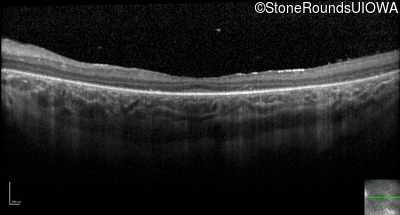

Optical Coherence Tomography - Left - 20/80

Exemplar / OCT Stack